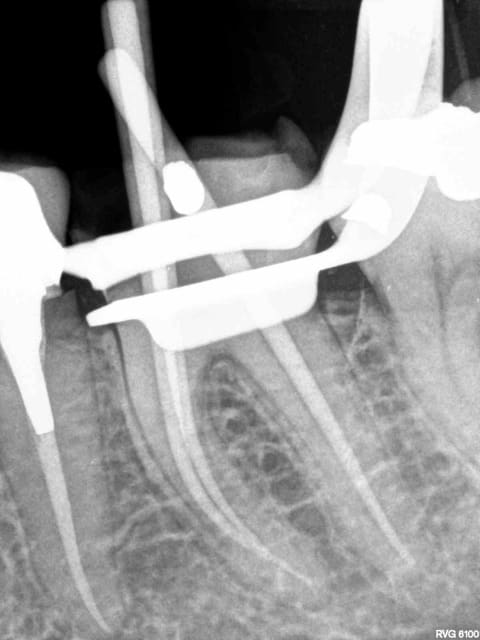

la première radio du fil est tenue au doigt. J'espère que c'est celui du patient.